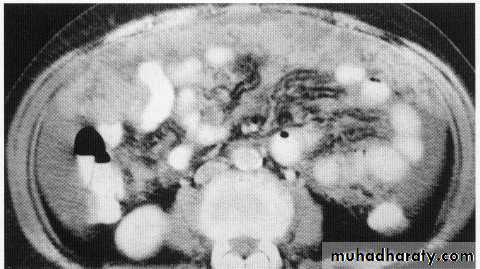

Peritoneal deposit

hepatic mets

hepatic mets,arterial phase

hepatic mets venous phase